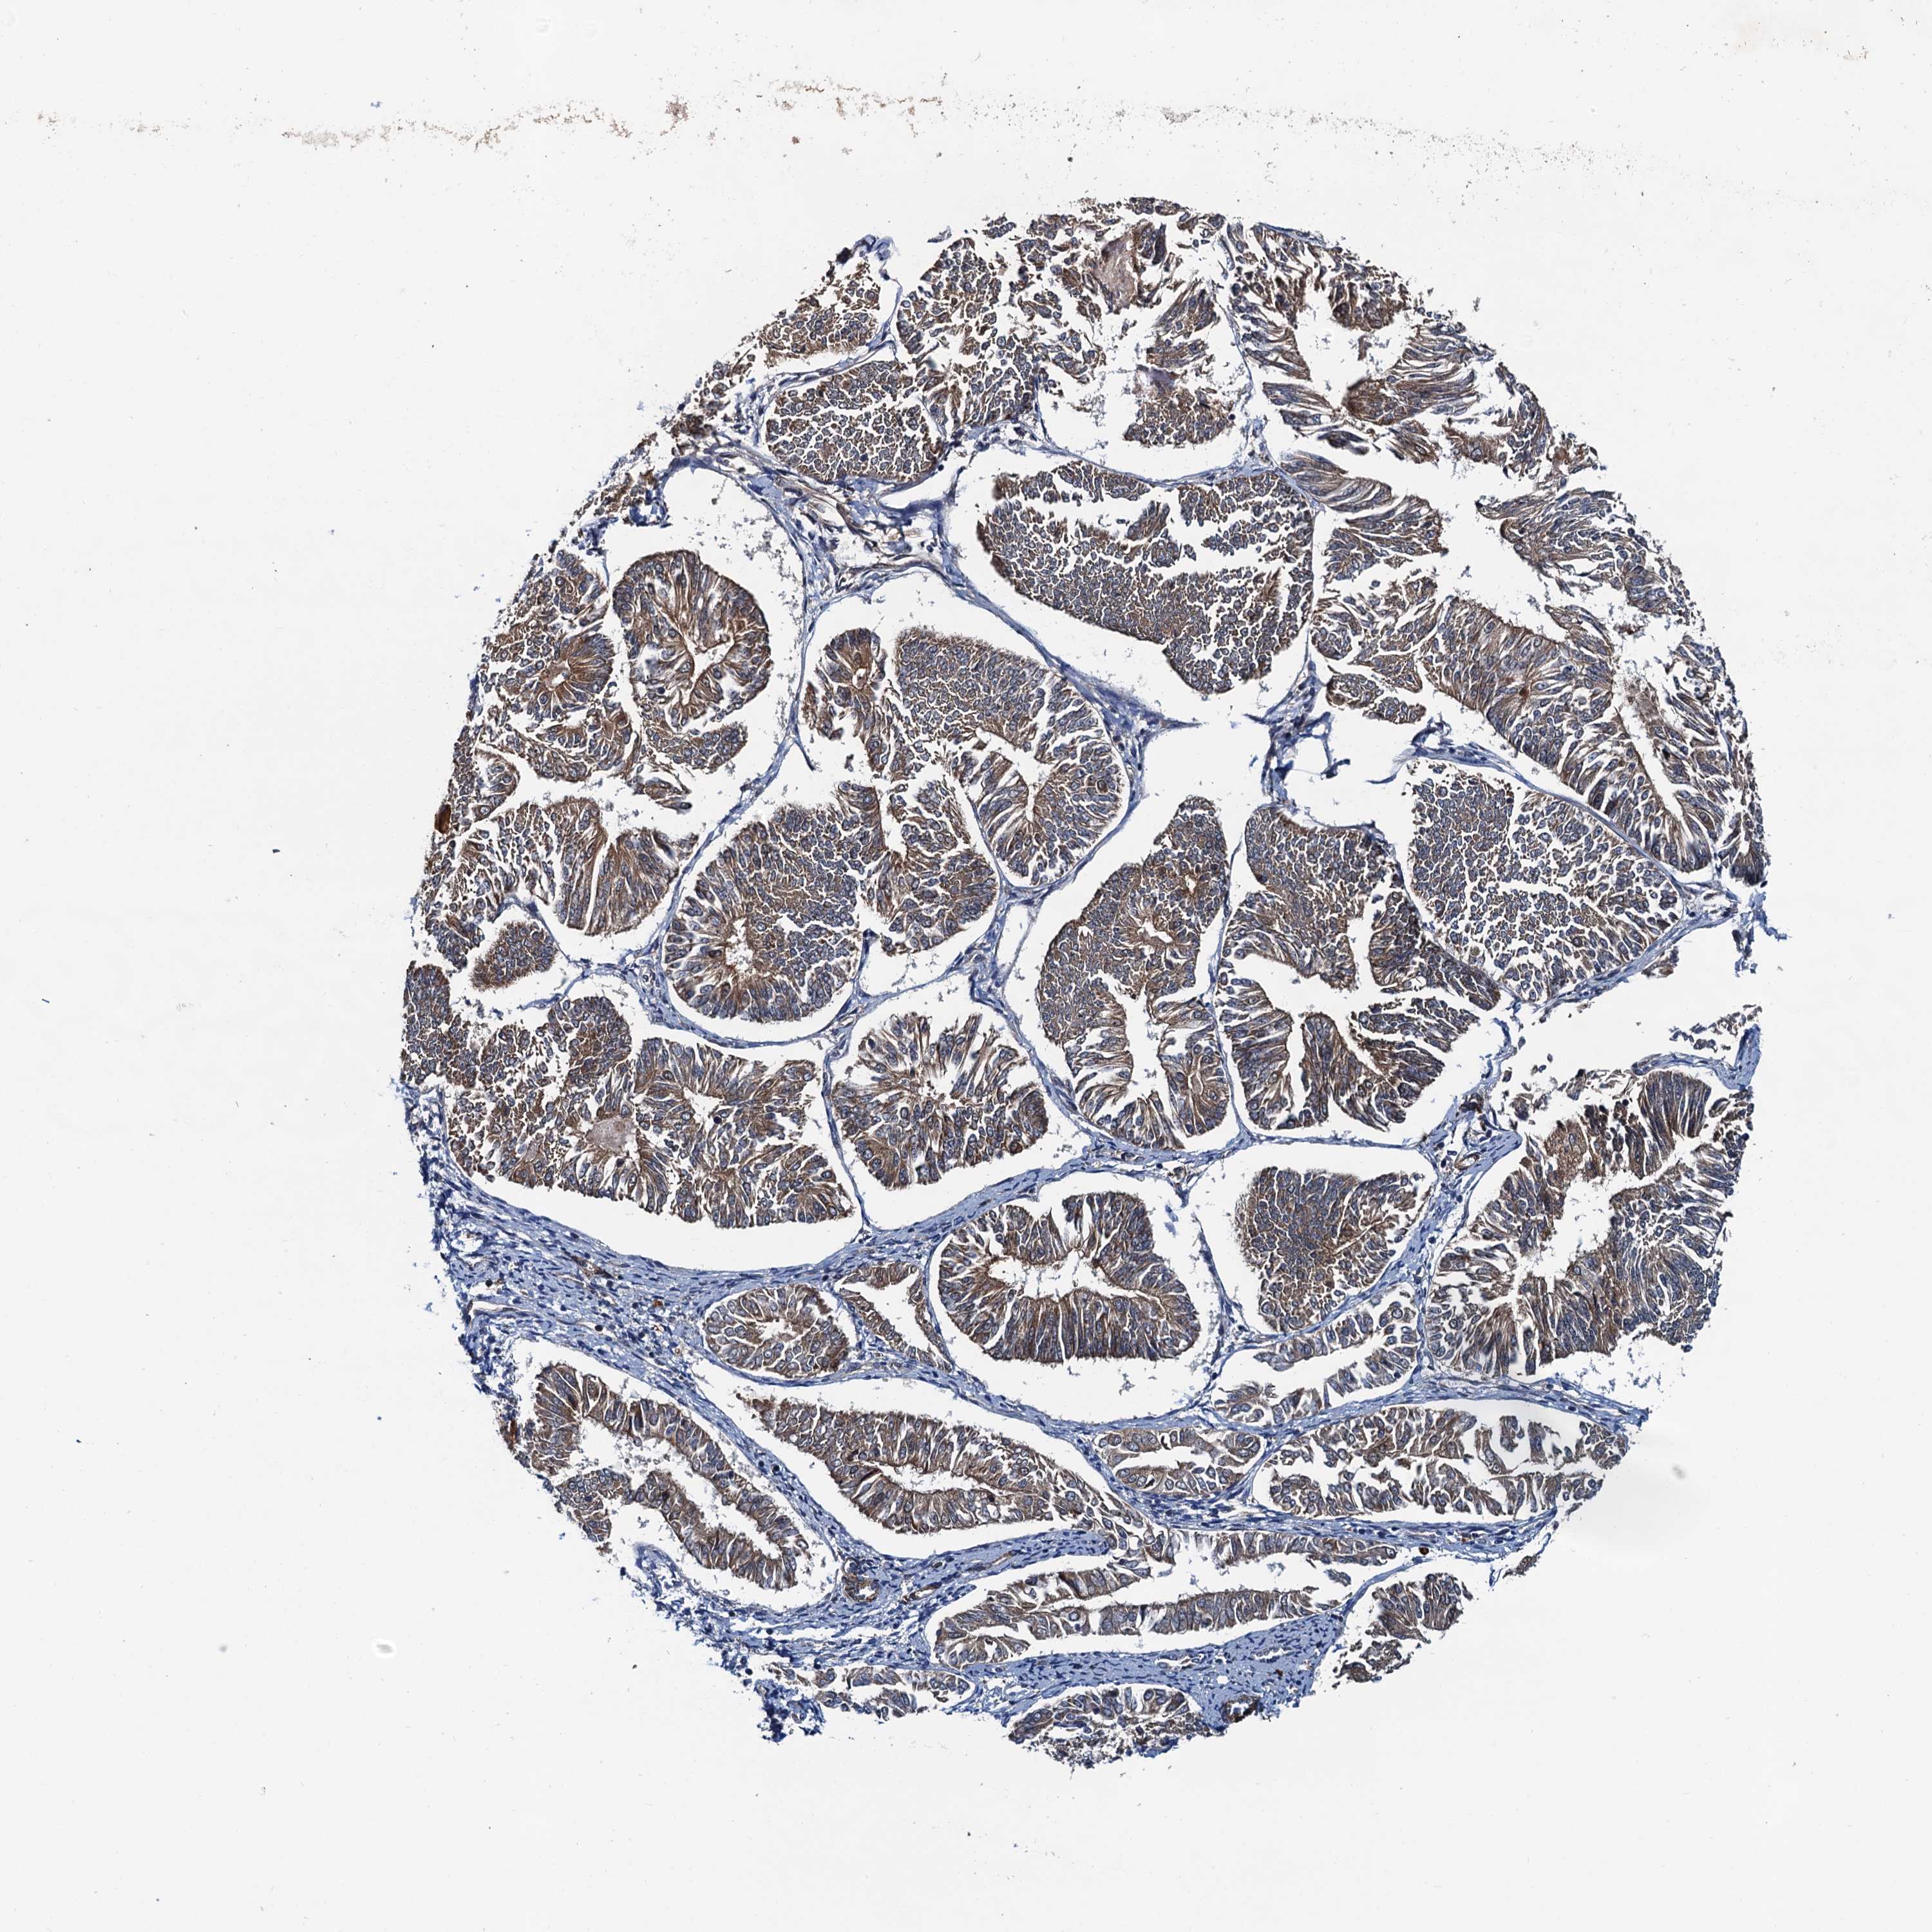

ENDOMETRIAL CANCER - Protein expressioni

A mouse-over function shows sample information and annotation data. Click on an image to view it in a full screen mode. Samples can be filtered based on level of antibody staining by selecting one or several of the following categories: high, medium, low and not detected. The assay and annotation is described here.

Note that samples used for immunohistochemistry by the Human Protein Atlas do not correspond to samples in the TCGA dataset.

Antibody stainingi

Antibody staining in the annotated cell types in the current human tissue is reported as not detected, low, medium, or high, based on conventional immunohistochemistry profiling in selected tissues. This score is based on the combination of the staining intensity and fraction of stained cells.

Each image is clickable and will lead to virtual microscopy that enables deeper exploration of all samples and also displays staining intensity scores, fraction scores and subcellular localization as well as patient and tissue information for each sample.

Antibody HPA039371

Antibody HPA040174

Staining

High

Medium

Low

Not detected

Intensity

Strong

Moderate

Weak

Negative

Quantity

>75%

75%-25%

<25%

None

Location

Nuclear

Cytoplasmic/membranous

Cytoplasmic/membranous,nuclear

Adenocarcinoma, NOS